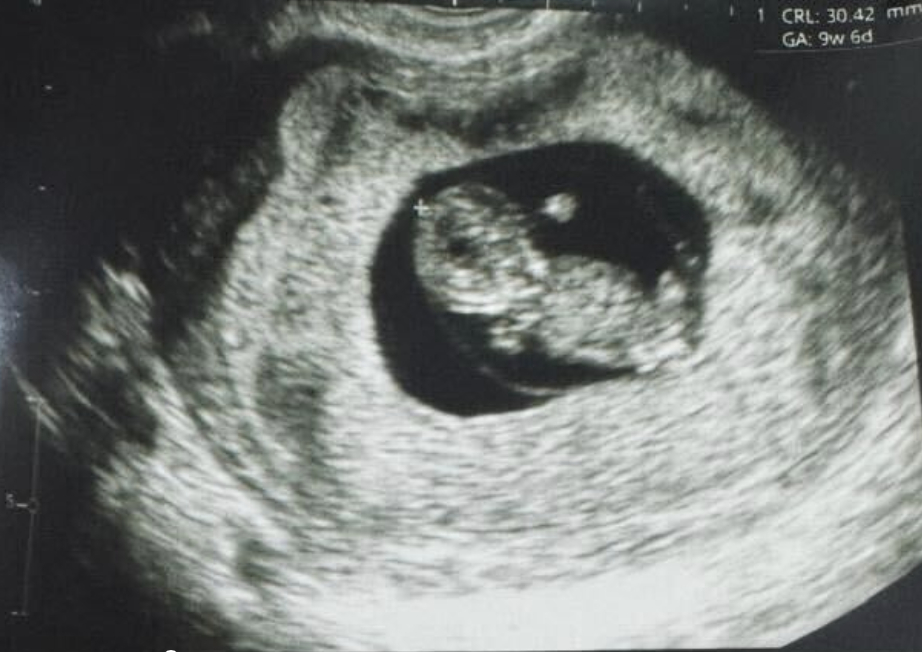

This follows their news in December of 2024, when they announced their first live birth, they’re currently enrolling participants for the Phase 3 trial here, and here’s the paper (it’s in pre-print).